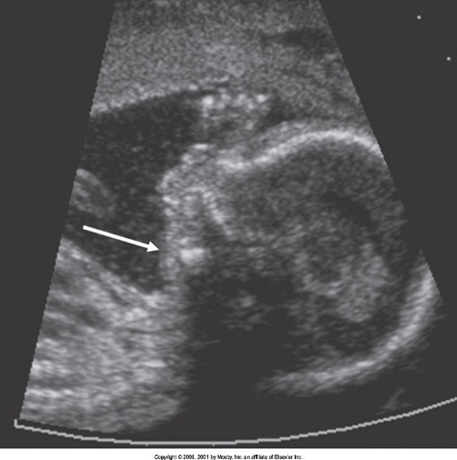

What are these images showing?

Micrognathia